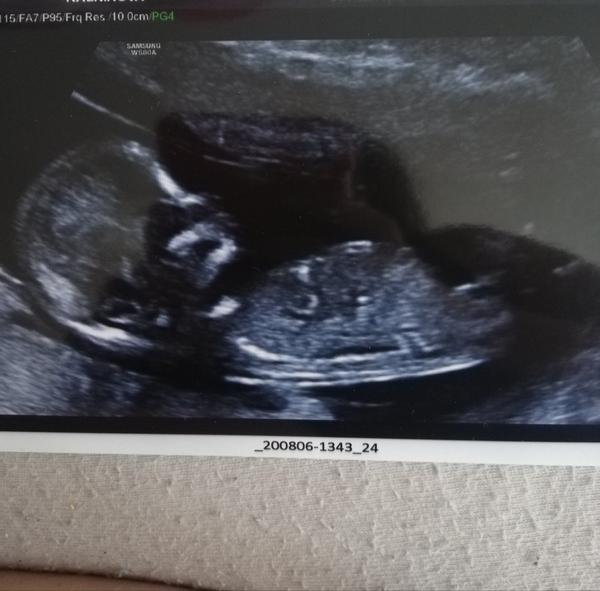

Je to holčička nebo chlapeček? Foto ultrazvuku

Mám další fotku do diskuze ☝️😃

@allisenka 100% 🙂 pohlavní hrbolek je hezky rovně. Na té minule fotce to jde vidět úplně krásně. Mám dvě holky a úplně stejné. Chlapečci mají hrbolek jakoby nahoru, jako by trčel 🙂

@allisenka kluk 😁

@almidrob2539 To není noha, to co já myslím, ale pupečník určitě. A pindík to není. Vypadá to fakt na holku i podle té další fotky 😉